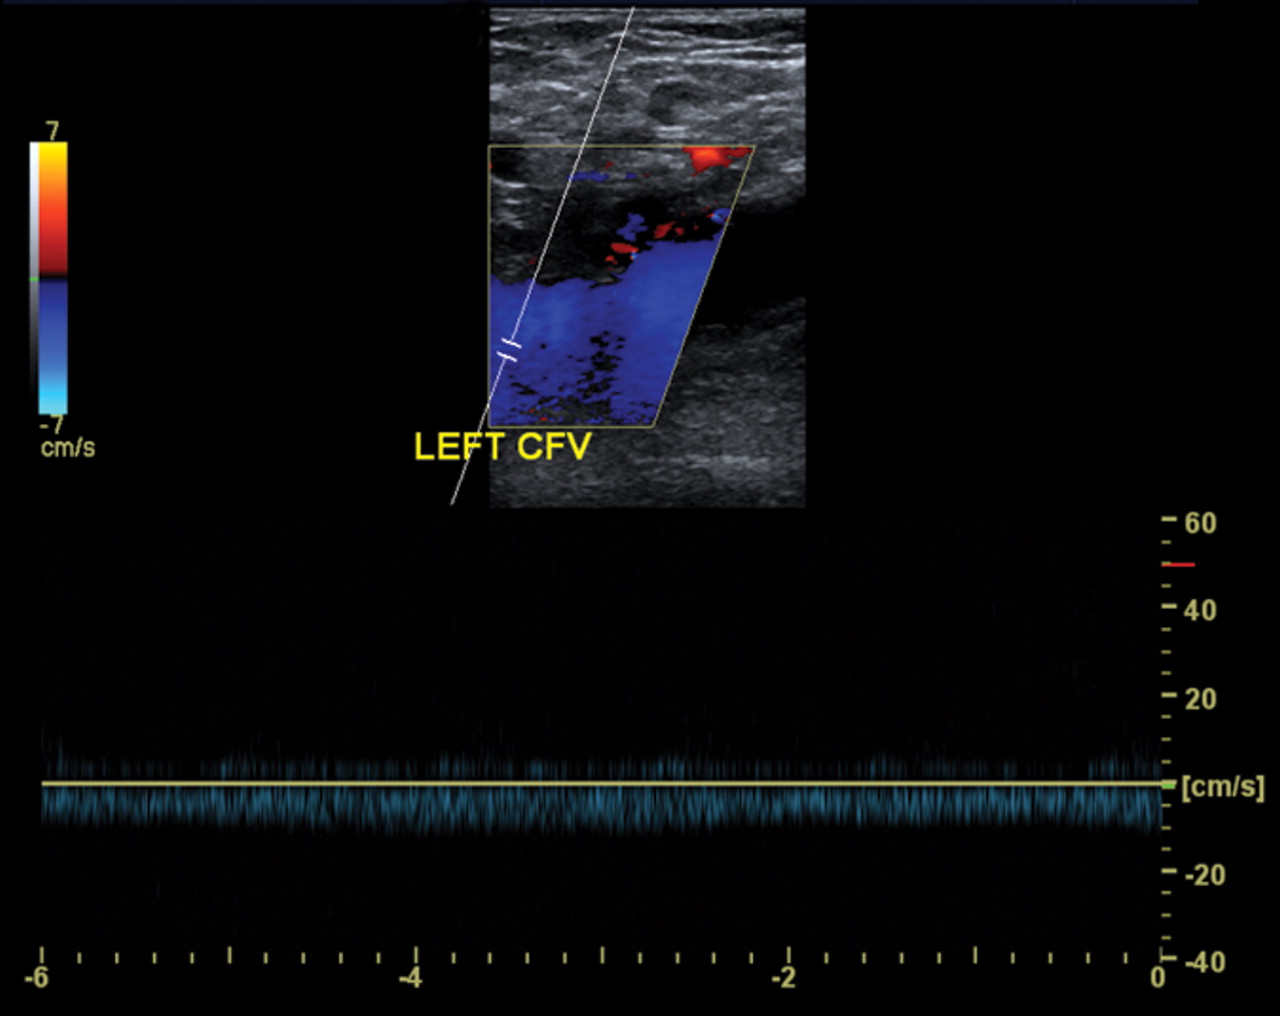

<p>what is being shown in this image?</p>

what is being shown in this image?

normal finding

52

proximal obstruction